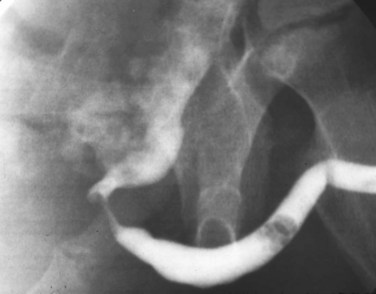

Young’s type I valves make up 95% of all posterior urethral obstructions (Fig. 126–2).

Figure 126–2 A, Voiding cystourethrogram demonstrates a typical type I posterior urethral valve with a dilated posterior urethra, elevated bladder neck, and valve leaflets obstructing the flow of contrast material from the bladder. B, This cystoscopic image from the distal urethra shows the valve leaflets forced into the lumen with the bladder full, illustrating their obstructive effect.